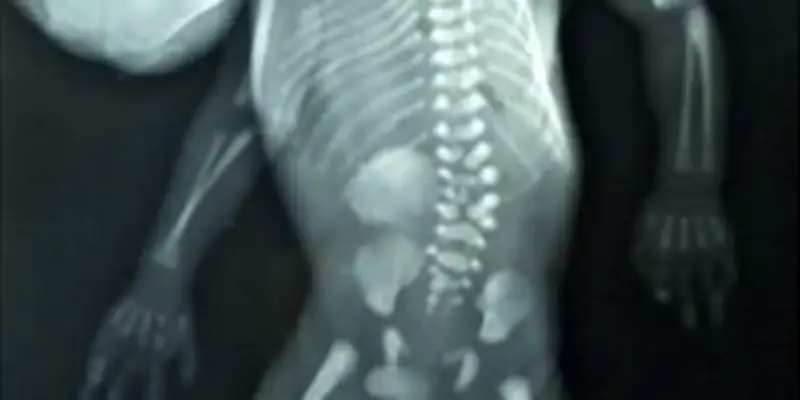

Le cas rapporté implique un jumeau qui a développé un fœtus parasite dans sa région oropharyngée, c'est-à-dire au niveau de la bouche et du pharynx. Cette condition, connue sous le nom de fœtus in fœtu, survient lorsqu'un embryon se forme à l'intérieur d'un autre pendant la grossesse, mais ne se développe pas complètement. Typiquement, le parasite est encapsulé et peut contenir des structures comme des os, des tissus mous, ou même des organes rudimentaires.

Dans cette instance spécifique, le fœtus parasite a été localisé dans la cavité buccale, ce qui est particulièrement inhabituel. Les médecins ont dû procéder à une intervention chirurgicale complexe pour extraire le parasite, tout en préservant la santé et la fonctionnalité de l'hôte. Cette opération a nécessité une équipe multidisciplinaire, incluant des chirurgiens, des pédiatres et des spécialistes en imagerie médicale.